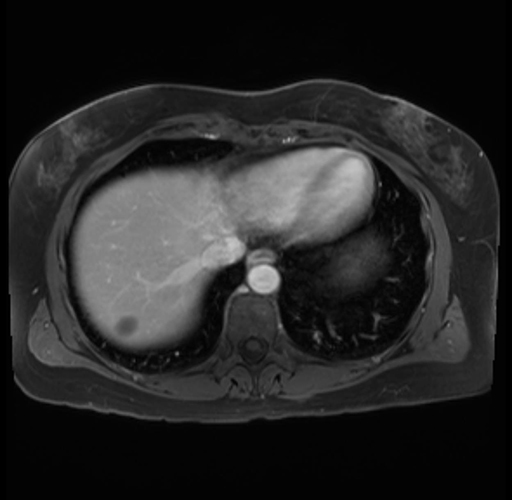

Imaging Analysis

Look through the patient's CT scan to identify any areas of concern for the necessary procedure.

Based on your CT findings, which issue(s) are present and would give reason for "planned slowing down moment(s)" in this case?